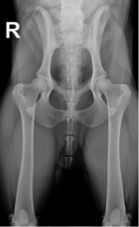

Für das PennHIP® Verfahren werden drei Röntgenaufnahmen angefertigt:

Bei der Distraktionsaufnahme wird ein sogenannter Distraktor zwischen die Beine des Tieres gelegt. Wenn der Untersucher die Beine des Hundes gegen den Distraktor drückt, wird der Oberschenkelkopf aus der Hüftpfanne „herausgezogen“. Je weiter das möglich ist, desto lockerer ist die Hüfte und desto größer die Wahrscheinlichkeit, dass ein Hund an einer HD leiden wird. Das Maß für die Lockerheit des Hüftgelenks ist dabei der Distraktionsindex (DI).

links: komprimiertes Hüftgelenk

rechts: distrahiertes Hüftgelenk